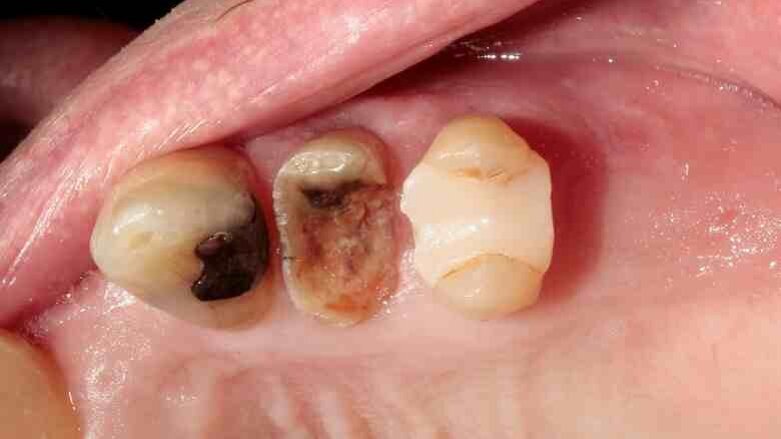

A 70-year-old female patient visited our clinic owing to a fractured maxillary first molar. Tooth #24 had previously had a large composite restoration that was no longer in place at the time of the dental appointment.

Tooth #24 was severely decayed down to the marginal bone edge.